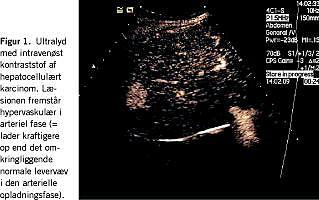

De hyppigst anvendte screeningsmetoder er α -føtoprotein og ultralydsskanning (Figur 1 ) [1, 3]. I en undersøgelse af screening randomiseredes knapt 19.000 patienter med kronisk hepatitis B [3]. I gruppen, der blev screenet hvert halve år med ultralyd og α-føtoprotein, var dødeligheden af HCC 83/ 100.000 observationsår, mod 131/100.000 i kontrolgruppen. I dette studie havde α-føtoprotein (ved en tærskelværdi på 20 ng/ml) en sensitivitet på 69% og en specificitet på 95%, ultralyd alene havde en sensitivitet på 84% og en specificitet på 97%, og kombinationen af de to havde både en sensitivitet og en specificitet på 92%. AASLD anbefaler ultralyd alene eller kombineret med α-føtoprotein [1].